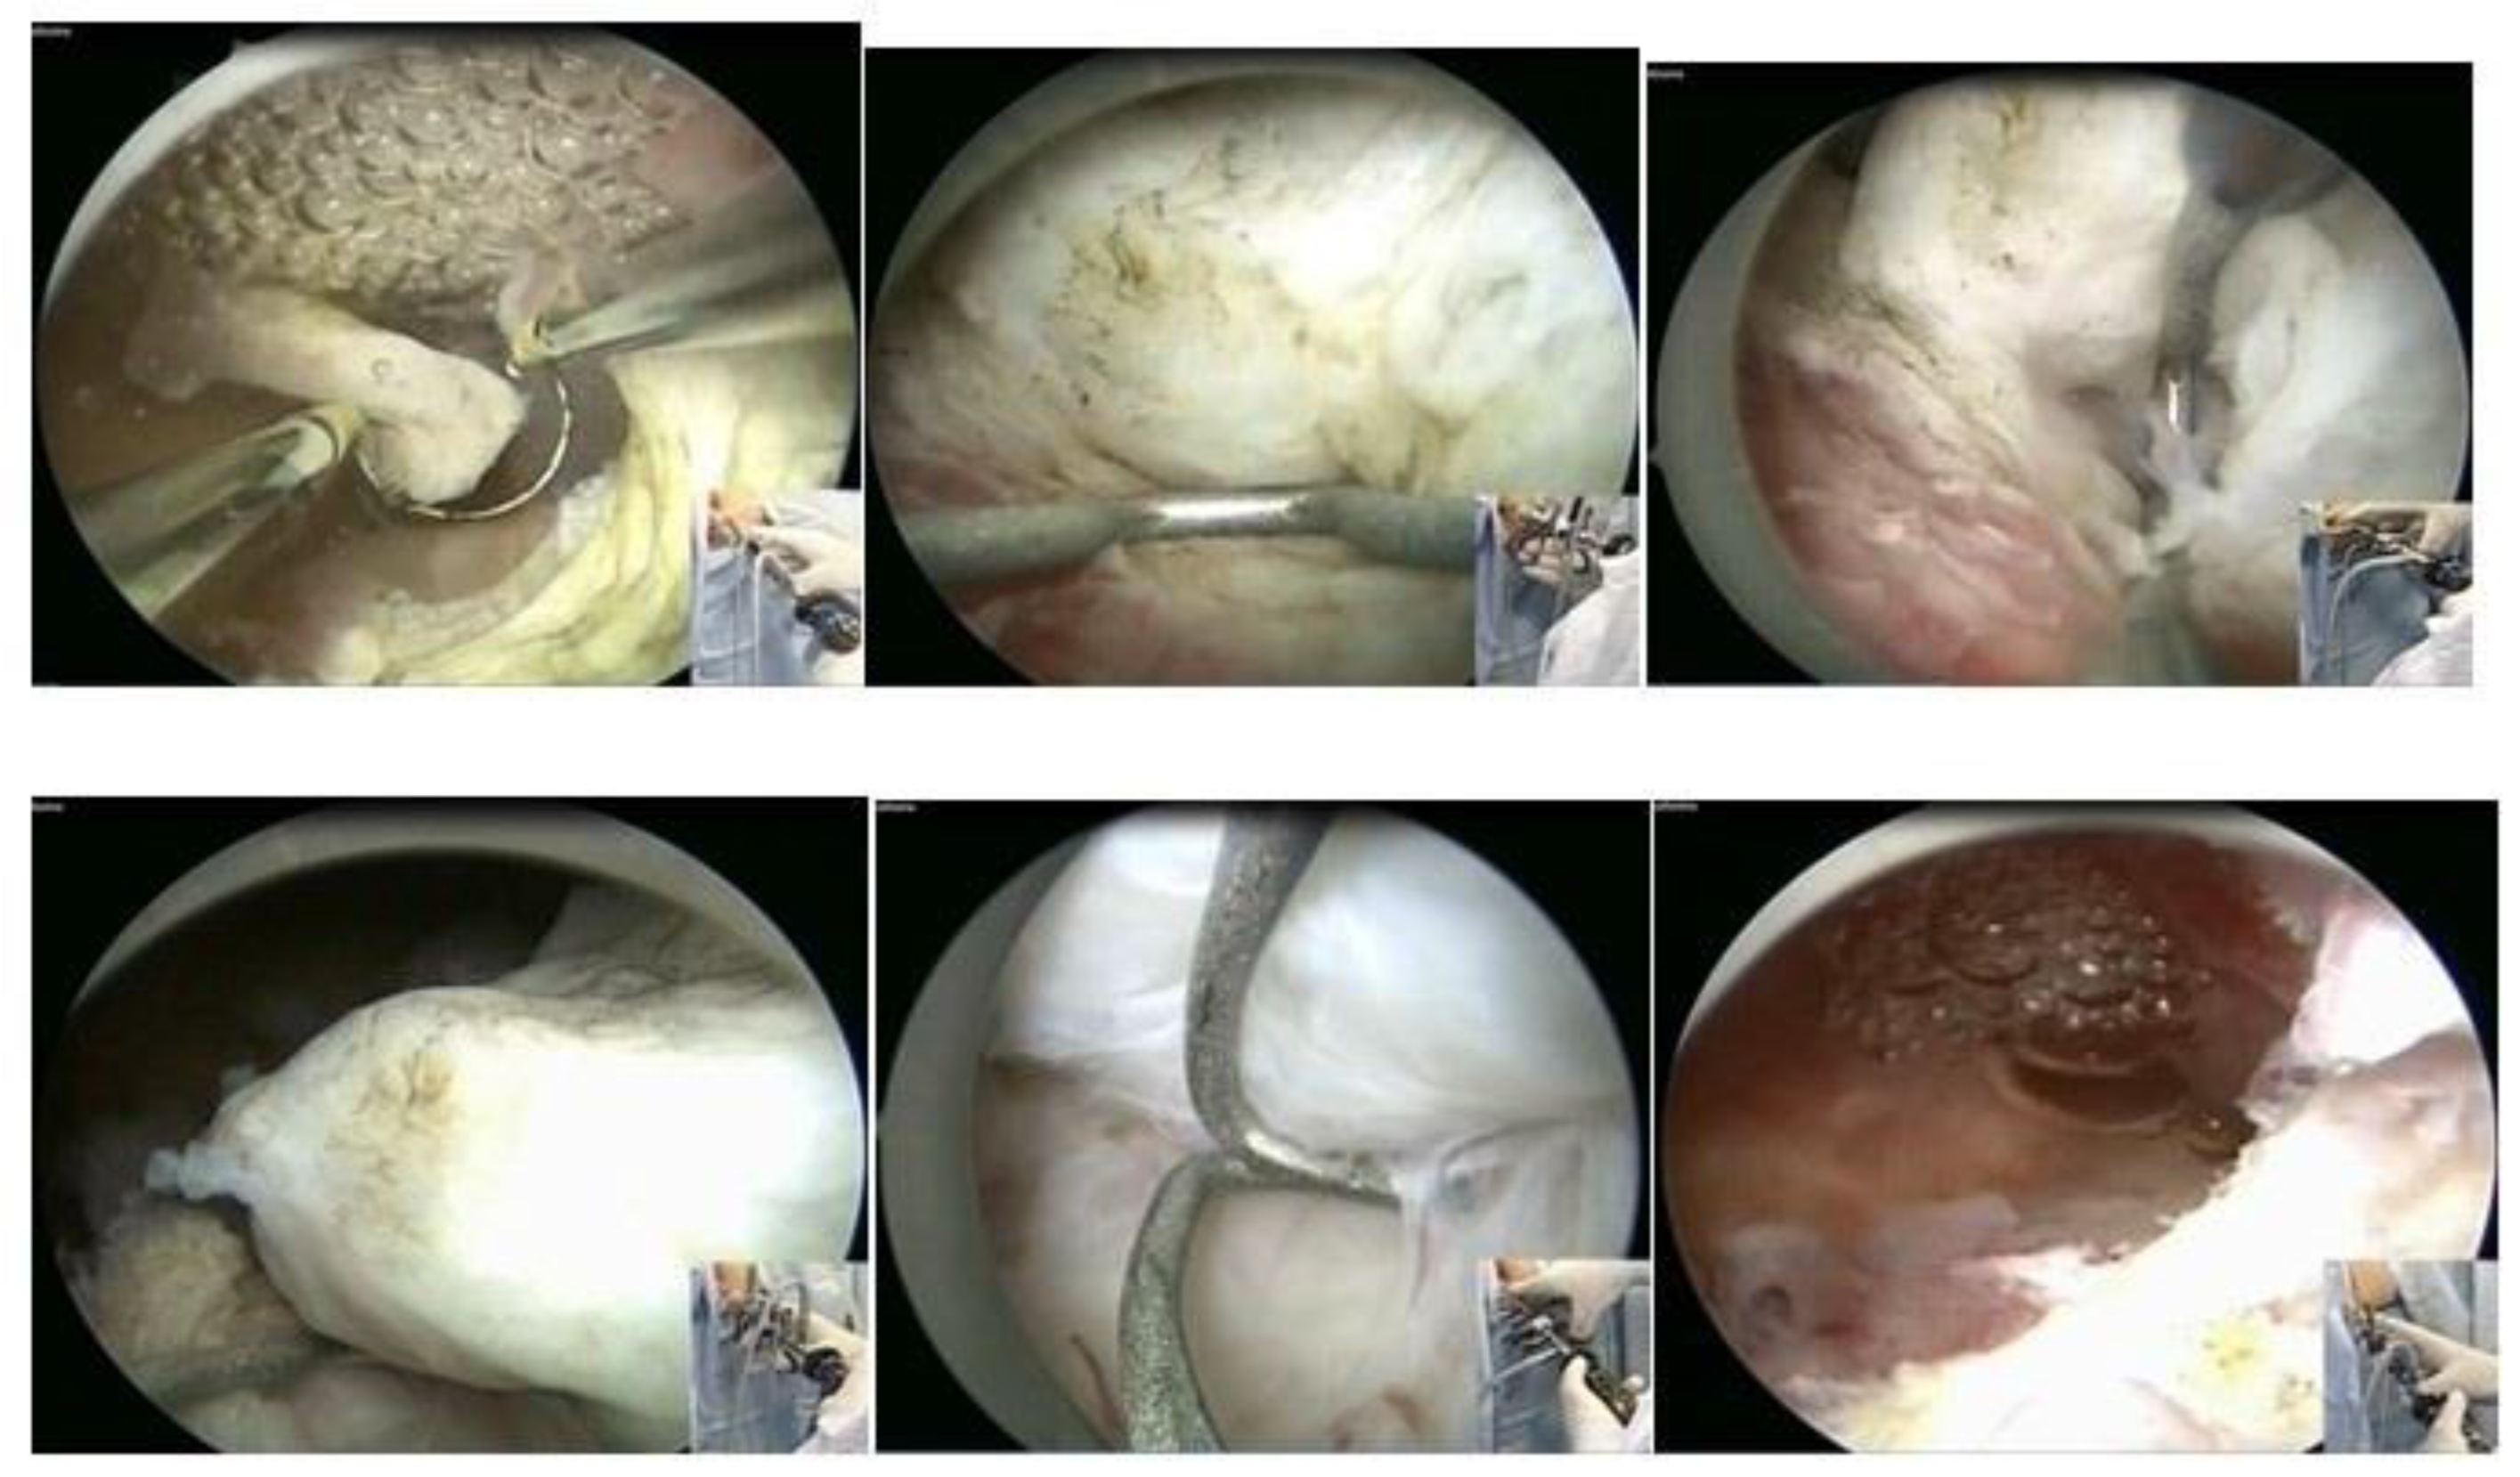

3.1. Hysteroscopic Myomectomy Techniques

Myomectomy, whether laparotomic or laparoscopic, is a well-established procedure, widely performed with the goal of uterine preservation. In both approaches, the myomectomy technique is the same: incision of the serosa up to the pseudocapsule, identification of the myoma, traction and movement of the nodule, assistance in dissecting the plane of the pseudocapsule within the myometrium, and enucleation of the myoma from the uterine wall. This fibroid enucleation technique is known and performed by all gynecologists. When the pseudocapsule is reached, the chance of preserving the uterus will be greater, with less bleeding and less myometrial damage, which differs from adenomyosis resection, which does not have a pseudocapsule [21] (Figure 6).

The presentation of the techniques will make the presentation of this text more didactic, as we basically have two techniques, which can be associated or isolated, each one having its own indication of excellence. These are the enucleation technique and the slicing or myolysis technique, all of which can be performed in outpatient and inpatient hysteroscopy. The enucleation technique was described by Mazzon in 1995 [24] and Lasmar in 2001 [25]. Both techniques have the same basis for enucleation of the nodule, but Mazzon fragments the nodule until it reaches its intramural portion and then uses a “cold loop” to mobilize the fibroid, while Lasmar enucleates the entire fibroid and then slices it. The technique is to incise the endometrium around the submucosal myoma to reach the pseudocapsule (Lasmar) or to reach this plane by slicing the myoma close to the myometrium (Mazzon). Arriving at the pseudocapsule, some fibrous beams must be sectioned. The mobilization of the myoma, from the outside to the center, from front to back, progressively frees it from the myometrium, without significant bleeding and without thermal damage, with a lower risk of intravasation, as it does not cut the myometrial vessels. The mobilization of the myoma with its enucleation can be performed by all instruments, without energy, the use of scissors or tweezers being more appropriate in the outpatient clinic and Collins loop or “cold loop” in hospital hysteroscopy. The slicing technique is based on the progressive cutting of the submucosal portion of the myoma, maintaining the fragmentation of the intramural portion, leading, in most cases, to greater removal of the endometrium and myometrium, with greater thermal damage and risk of intravasation [26]. Fragmentation of the myoma can be performed with a semi-circle loop, with mono or bipolar energy, LASER fiber or morcellator. Thus, the technique of excellence in hysteroscopic myomectomy is the enucleation of the intramural portion of the submucosal myoma, mobilizing the nodule and separating it from the wall of the uterus, while fragmentation would deal with the removal of the myoma from the uterine cavity.

In our service, the most performed technique is using the 5 Fr tweezers or scissors. Initially, the endometrium is incised around the nodule until accessing the plane of the pseudocapsule; then, with the forceps or the body of the hysteroscope, entering between the nodule and the myometrium, the release is initially performed, laterally first and then centrally, until its complete release (Figure 7).

At the end, the nodule will be loose in the cavity and can be fragmented or completely removed with grasping forceps. In cases of difficulty in removing the nodule from the cavity, the patient should be instructed to return in 7 to 10 days, during which time either the nodule will be spontaneously expelled by the patient—she should be oriented about this possibility—or it will have drastically decreased in size, allowing its removal.

When using instruments with energy, we can use the bipolar Collins loop of a miniresectosope system [26] (Figure 8) or the LASER fiber to incise the endometrium around the myoma. However, all mobilization is performed mechanically with forceps, a loop, or the resectoscope itself.

Figure 6. Laparotomic and laparoscopic myomectomy preserving pseudocapsule.

Figure 7. Office hystreroscopic myomectomy with scissor.

Figure 8. Office hysteroscopic myomectomy with miniresectoscope.